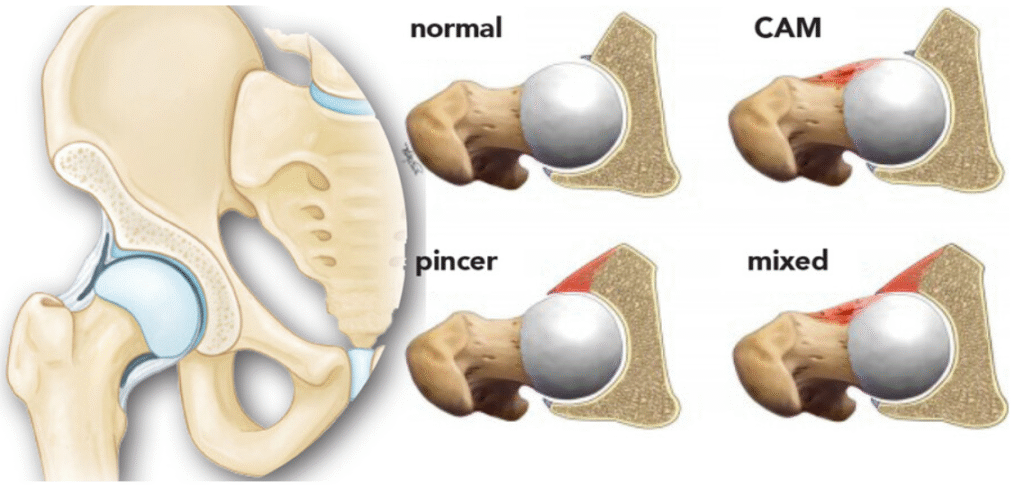

- Types of FAI: Cam, Pincer, and Mixed

1. Cam Morphology

- Occurs when the femoral head is not perfectly round.

- Leads to abnormal contact with the acetabulum during hip flexion.

2. Pincer Morphology

- Results from acetabular overcoverage.

- The acetabular rim extends too far, compressing the labrum.

3. Combined (Mixed) Morphology

- A combination of cam and pincer features.

- Seen in approximately 85% of symptomatic FAI cases.